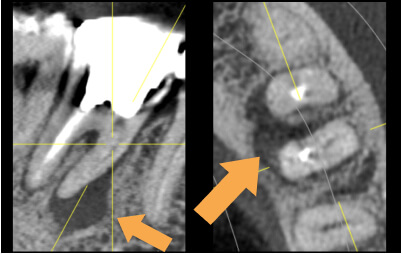

精密根管治療症例

術前

治療中

矢印部が処置されていない

術後

矢印部に大きな骨吸収像

根管を清掃した後

骨の再生が見られる

| 主訴 | 噛むと違和感がある。 レントゲンで根の先に黒い影を指摘された。 |

|---|---|

| 治療期間 | 根管治療3回 補綴治療3回 |

| 治療費 |

(ファイバーコア・ジルコニアクラウン) |

| 治療内容 |

通法の根管治療を行いました。ラバーダム防湿、 マイクロスコープ下で未処置であった根管を発見し処置。 |

| 治療のリスク |

治療直後は反応性に一時的な腫れや痛みが出る可能性があります。 根管治療で改善が見られない場合は外科的根管治療が必要になる場合があります。 |